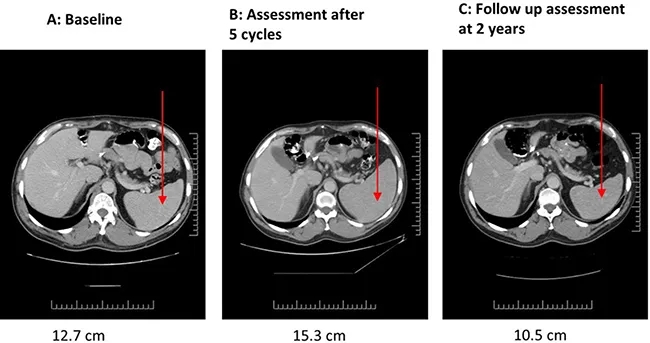

NK-92治疗前的CT扫描显示:双侧腋窝最大淋巴结长径达2.5cm,同时存在1cm大小的肠系膜淋巴结及腹主动脉旁淋巴结(图1A)。第1疗程NK-92治疗第23天中期评估显示病情稳定,最大腋窝淋巴结略缩小;3个疗程后影像学提示部分淋巴结缩小、部分增大(图1B);5个疗程后淋巴结持续增大,且脾脏从基线12.7cm(图2A)增大至15.3cm(图2B),因影像学提示疾病进展,患者停止治疗。停药后患者未接受其他抗癌治疗,CT扫描随访发现,24个月后所有病灶均消退(图1D、1E,图2C)。后续患者曾因降压药出现血小板减少症(经泼尼松+环孢素治疗好转),约1年后因皮肤带状疱疹感染继发急性播散性脱髓鞘性脑脊髓炎(经激素治疗后,6个月缓慢减量,神经功能完全恢复)。此后患者未再接受抗癌治疗,入组试验10年后的最近一次随访显示,其临床与影像学检查均无疾病迹象,且无任何不适症状。

▼图2 患者03在NK-92细胞治疗前后脾脏的CT对比

▲图源“Oncotarget”,版权归原作者所有,如无意中侵犯了知识产权,请联系我们删除